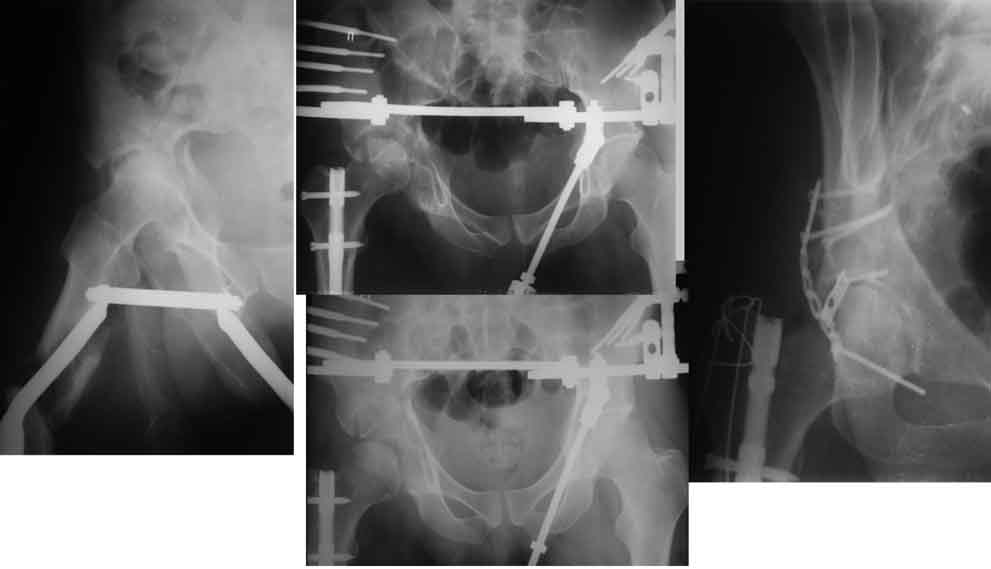

Глубокоуважаемые коллеги! Благодарю за полезные советы, которые нам очень помогли в выборе оперативной тактики пациента. 13.02.08 мы выполнили первый этап оперативного лечения этого больного. Вначале зафиксировали левое бедро АВФ Гофмана

(главный травматолог области достал из каких-то «анналов», первый раз в жизни увидел этот аппарат в живую). После наложения «ДРУ Челнокова» выполнили ЗИО правого бедра реконструктивным штифтом Chm. Далее уложили пациента на левый бок и выполнили остеосинтез вертлужной впадины. Ограничились задне-латеральным доступом без отсечения вертела, чтобы не утяжелять операцию. Результат прилагается.

Следующим этапом планируем выполнить ЗИО левого бедра.

1. укорочение левой н\конечности составляет 3 см. Необходимо ли думать об этом сейчас, или вернуться к устранению укорочения после консолидации перелома?

2. сохраняется некоторое смещение переднего отдела вертлужной впадины, нужно ли его устранить?

И смещение передней колонны вроде бы не критично.

Если можно пошли три проекции и побольше размером,